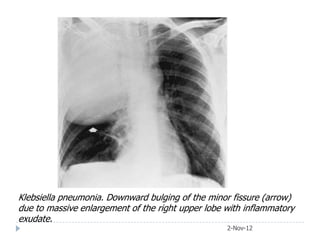

Klebsiella pneumonia. Downward bulging of the minor fissure (arrow)

due to massive enlargement of the right upper lobe with inflammatory

exudate.

• #40 This x-ray shows a large lobar density in the right upper lobe with some area of incomplete consolidation in the density. The lower end of this opacity is bulging and the horizontal fissure is displaced downward.The lateral confirms large right upper lobe pneumonia with a bulging fissure seen in a densely consolidated lobe due to klebsiella pneumonia.